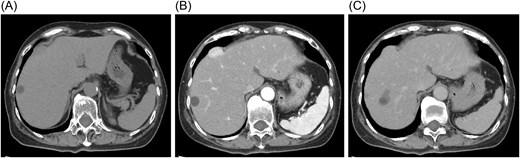

Contrast-enhanced computed tomography (CT) showed a mass located beneath the hepatic dome in segment 8, protruding extrahepatically (Fig. 2A). The hepatic margin appeared mildly blunted, suggesting chronic liver changes. The lesion exhibited early enhancement in the arterial phase with prolonged enhancement into the equilibrium phase and only weak washout, findings atypical for hepatocellular carcinoma (Fig. 2B and C).

Contrast-enhanced computed tomography findings. (A) The mass is located beneath the hepatic dome in segment 8 and protrudes extrahepatically. (B) The lesion shows early enhancement in the arterial phase. (C) Prolonged enhancement persists into the equilibrium phase without obvious washout.